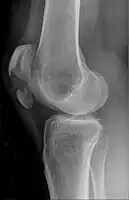

Comminuted fracture of patella

Osteochondral fracture of patella